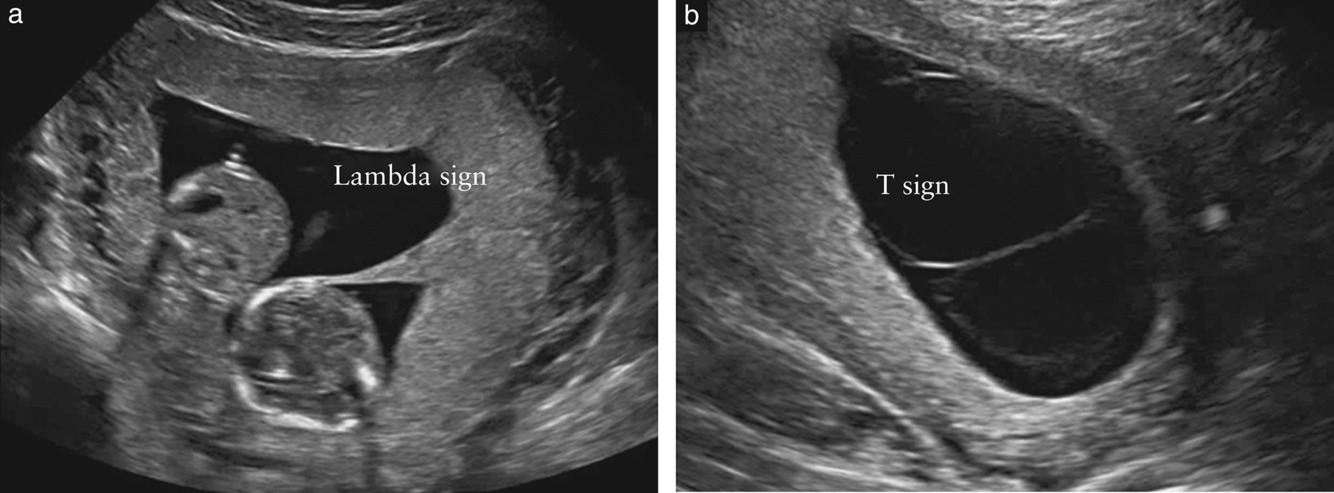

what is seen on ultrasound scan for dichorionic diamniotic twins?

have a membrane between the twins with a lambda sign or twin peak sign. this is the triangular appearance where the membrane between the twins meets the chorion as the chorion blends partially with the membrane

Q

have a membrane between the twins with a T sign. the T sign refers to where the membrane between the twins abruptly meets the chorion giving the T appearance

what is seen on ultrasound of monochorionic monoamniotic twins?

no membrane separating the twins